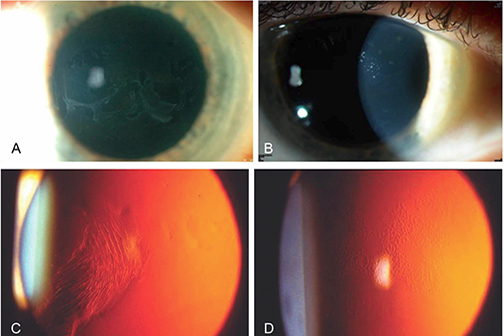

LSU Health New Orleans Develops New Human Cell Line to Study Blinding Eye Disorders

Under the direction of Boyd Professor Nicolas Bazan, MD, PhD, scientists at LSU Health New Orleans Neuroscience Center of Excellence have developed a new, experimental human cell line from retinal pigment epithelial cells. Called ABC, these cells so closely resemble and retain the properties of native retinal pigment epithelial (RPE) cells, the research team has shown that they are a reliable cell system to study retinal degenerative diseases. More

LSU Health Contributes to Research Suggesting Late-Onset Retinal Degeneration Mechanism & Potential Rx

A study led by the National Eye Institute (NEI) that included five researchers from the Bazan Lab at the LSU Health New Orleans Neuroscience Center of Excellence has discovered how late-onset retinal degeneration can develop and a surprising potential therapeutic -- metformin. The results are published online in Communications Biology, a Nature journal. More

LSU Health New Orleans Researchers Discover a Key Failure in AMD that May Lead to Progression & Vision Loss

Research led by Nicolas Bazan, MD, PhD, Boyd Professor, Ernest C. and Yvette C. Villere Chair for the Study of Retinal Degeneration, and Director of the Neuroscience Center of Excellence at LSU Health New Orleans School of Medicine, suggests that age-related macular degeneration (AMD) decreases an essential fatty acid, preventing the formation of a class of protective molecules and reducing repair potential. The discovery may also open new therapeutic avenues for AMD. More

LSU Health New Orleans’ Bazan Named to Ophthalmologist’s 2022 Power List sm.jpg)

Haydee E. P. Bazan, PhD, Professor of Neuroscience, Ophthalmology, Biochemistry and Molecular Biology at LSU Health New Orleans School of Medicine, has been named to the Ophthalmologist Power List 2022. According to the magazine, the list features “the Top 100 most influential people in the world of ophthalmology” and includes “genuine giants of clinical practice and vision research – and each one was nominated by you and then plucked from the long list of 450 names by our international panel of 20 judges.” More